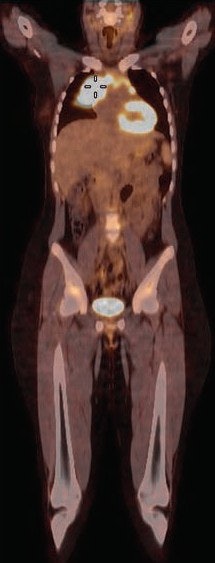

FDG-PET/CT can play a valuable role in directing image-guided biopsies of pediatric cancer patients, given its ability to detect and discern between malignant and benign regions, according to a study by a group from Saudi Arabia and Canada published in the March issue of the American Journal of Roentgenology.

Among some four dozen pediatric patients with known or suspected malignancies, the researchers found 36 cases in which FDG-PET images were concordant with biopsy results, and only one case of disagreement. The findings suggest FDG-PET/CT would be useful in identifying the best site for biopsy in young patients, the group concluded (AJR, March 2017, Vol. 208:3, pp. 656-662).

Forty-five subjects were imaged on a 16-slice PET/CT scanner (Gemini GXL, Philips Healthcare) in the supine position with normal respiration. Whole-body imaging began 60 minutes after injection of 5.2 MBq/kg of body weight of FDG, up to a maximum of 370 MBq (10 mCi).

Among the 47 FDG-PET/CT scans, 39 (83%) showed an abnormal increase of activity at the site of biopsy. In other words, the FDG-PET result was positive, as indicated by a median SUVmax of 6.5 (range, 1.0-21.3). The remaining eight scans revealed no areas of increased activity.

Of those 39 FDG-PET/CT scans which revealed abnormal increased activity, diagnostic results were achieved in 32 cases (82%). And of those 32 diagnostic biopsies, 21 results (66%) yielded a malignant diagnosis with an average SUVmax of 6.8, compared with 11 benign diagnoses with an average SUVmax of 3.2.